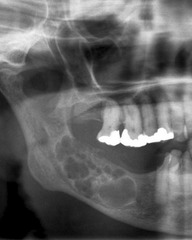

This type of cyst is also known as a periapical cyst; it occurs on non-vital teeth (infection); teeth with severe decay; pt. will complain of pain when biting down TX = extraction or Root Canal

Front

Radicular